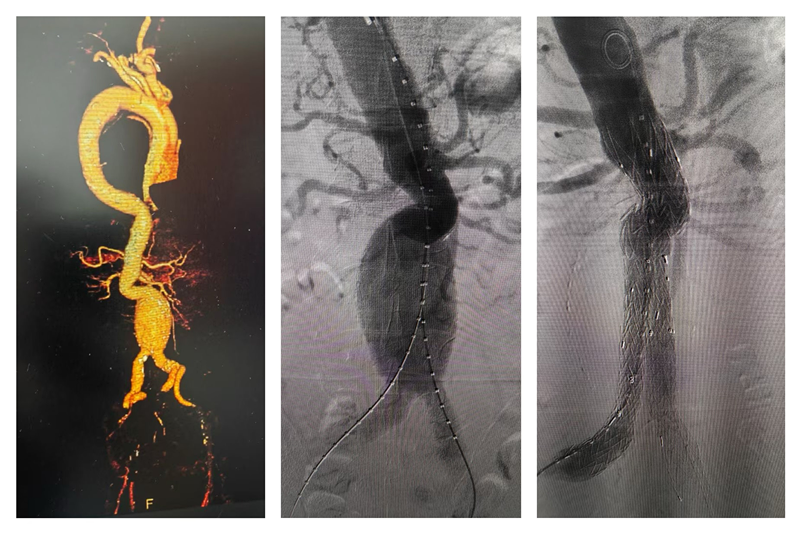

一名腹主动脉穿透溃疡并壁间血肿患者因急性胸腹痛入院,入院后胸心血管外科团队在黄小龙主任的带领下行腹腔干开窗点式隔绝,精准定位,不仅能为患者节省费用,手术达到良好效果,术后患者病情稳定,一周后患者康复出院。

黄伯伯因突发剧烈的背部撕裂样痛,被家人紧急送至我院胸心血管外科就诊,急查主动脉CTA显示:主动脉夹层壁间血肿(Stanford B型),并伴有穿透性溃疡。入院后胸心血管外科团队成功为患者开展Castor分支型主动脉覆膜支架手术,术后经过观察治疗,患者于十天后康复出院。